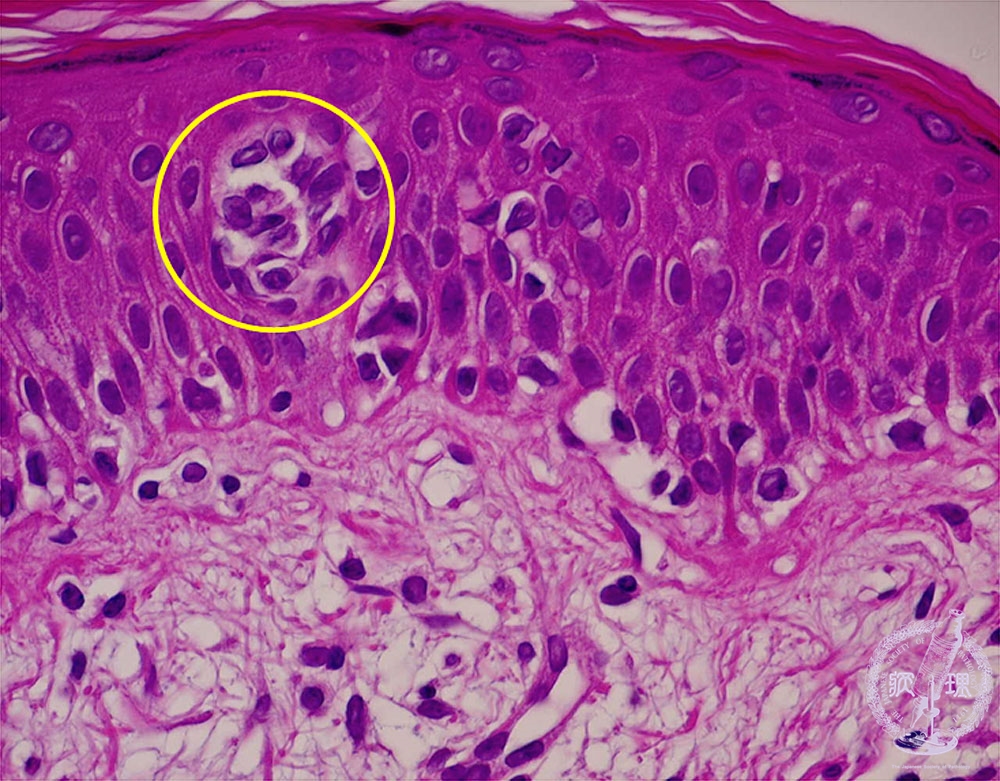

- (11)Malignant lymphoma of the skin (Mycosis fungoides)

Atypical lymphocytes infiltrate the epidermis with a microabscess (inside a circle).